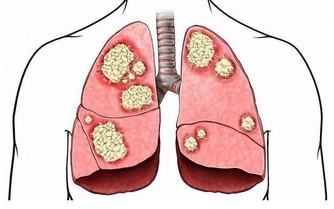

9. 狼瘡狼瘡是一種自身免疫性疾病,影響身體的許多系統和器官,皮膚也包含在內。該病的早期症狀之一,是在臉頰和鼻樑處出現蝴蝶形狀的紅棕色皮疹。當病情爆發時,皮疹看起來像是臉被曬傷了,這種皮疹的醫學術語是顴骨皮疹。狼瘡是一種需要看醫生的病症,它無法治愈,但治療可以幫助減少發作次數以及減少並發症。